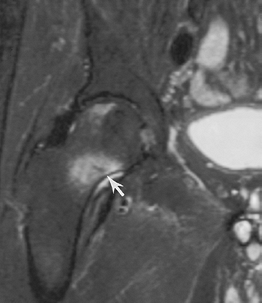

FIGURE 4-20 Radiographs of insufficiency fractures. (A) Radiograph demonstrates subtle bone condensation in the sacrum (arrow) caused by an insufficiency fracture. (B) AP radiograph of the pelvis with linear condensation in the left acetabulum (arrow) caused by an acetabular insufficiency fracture.

|